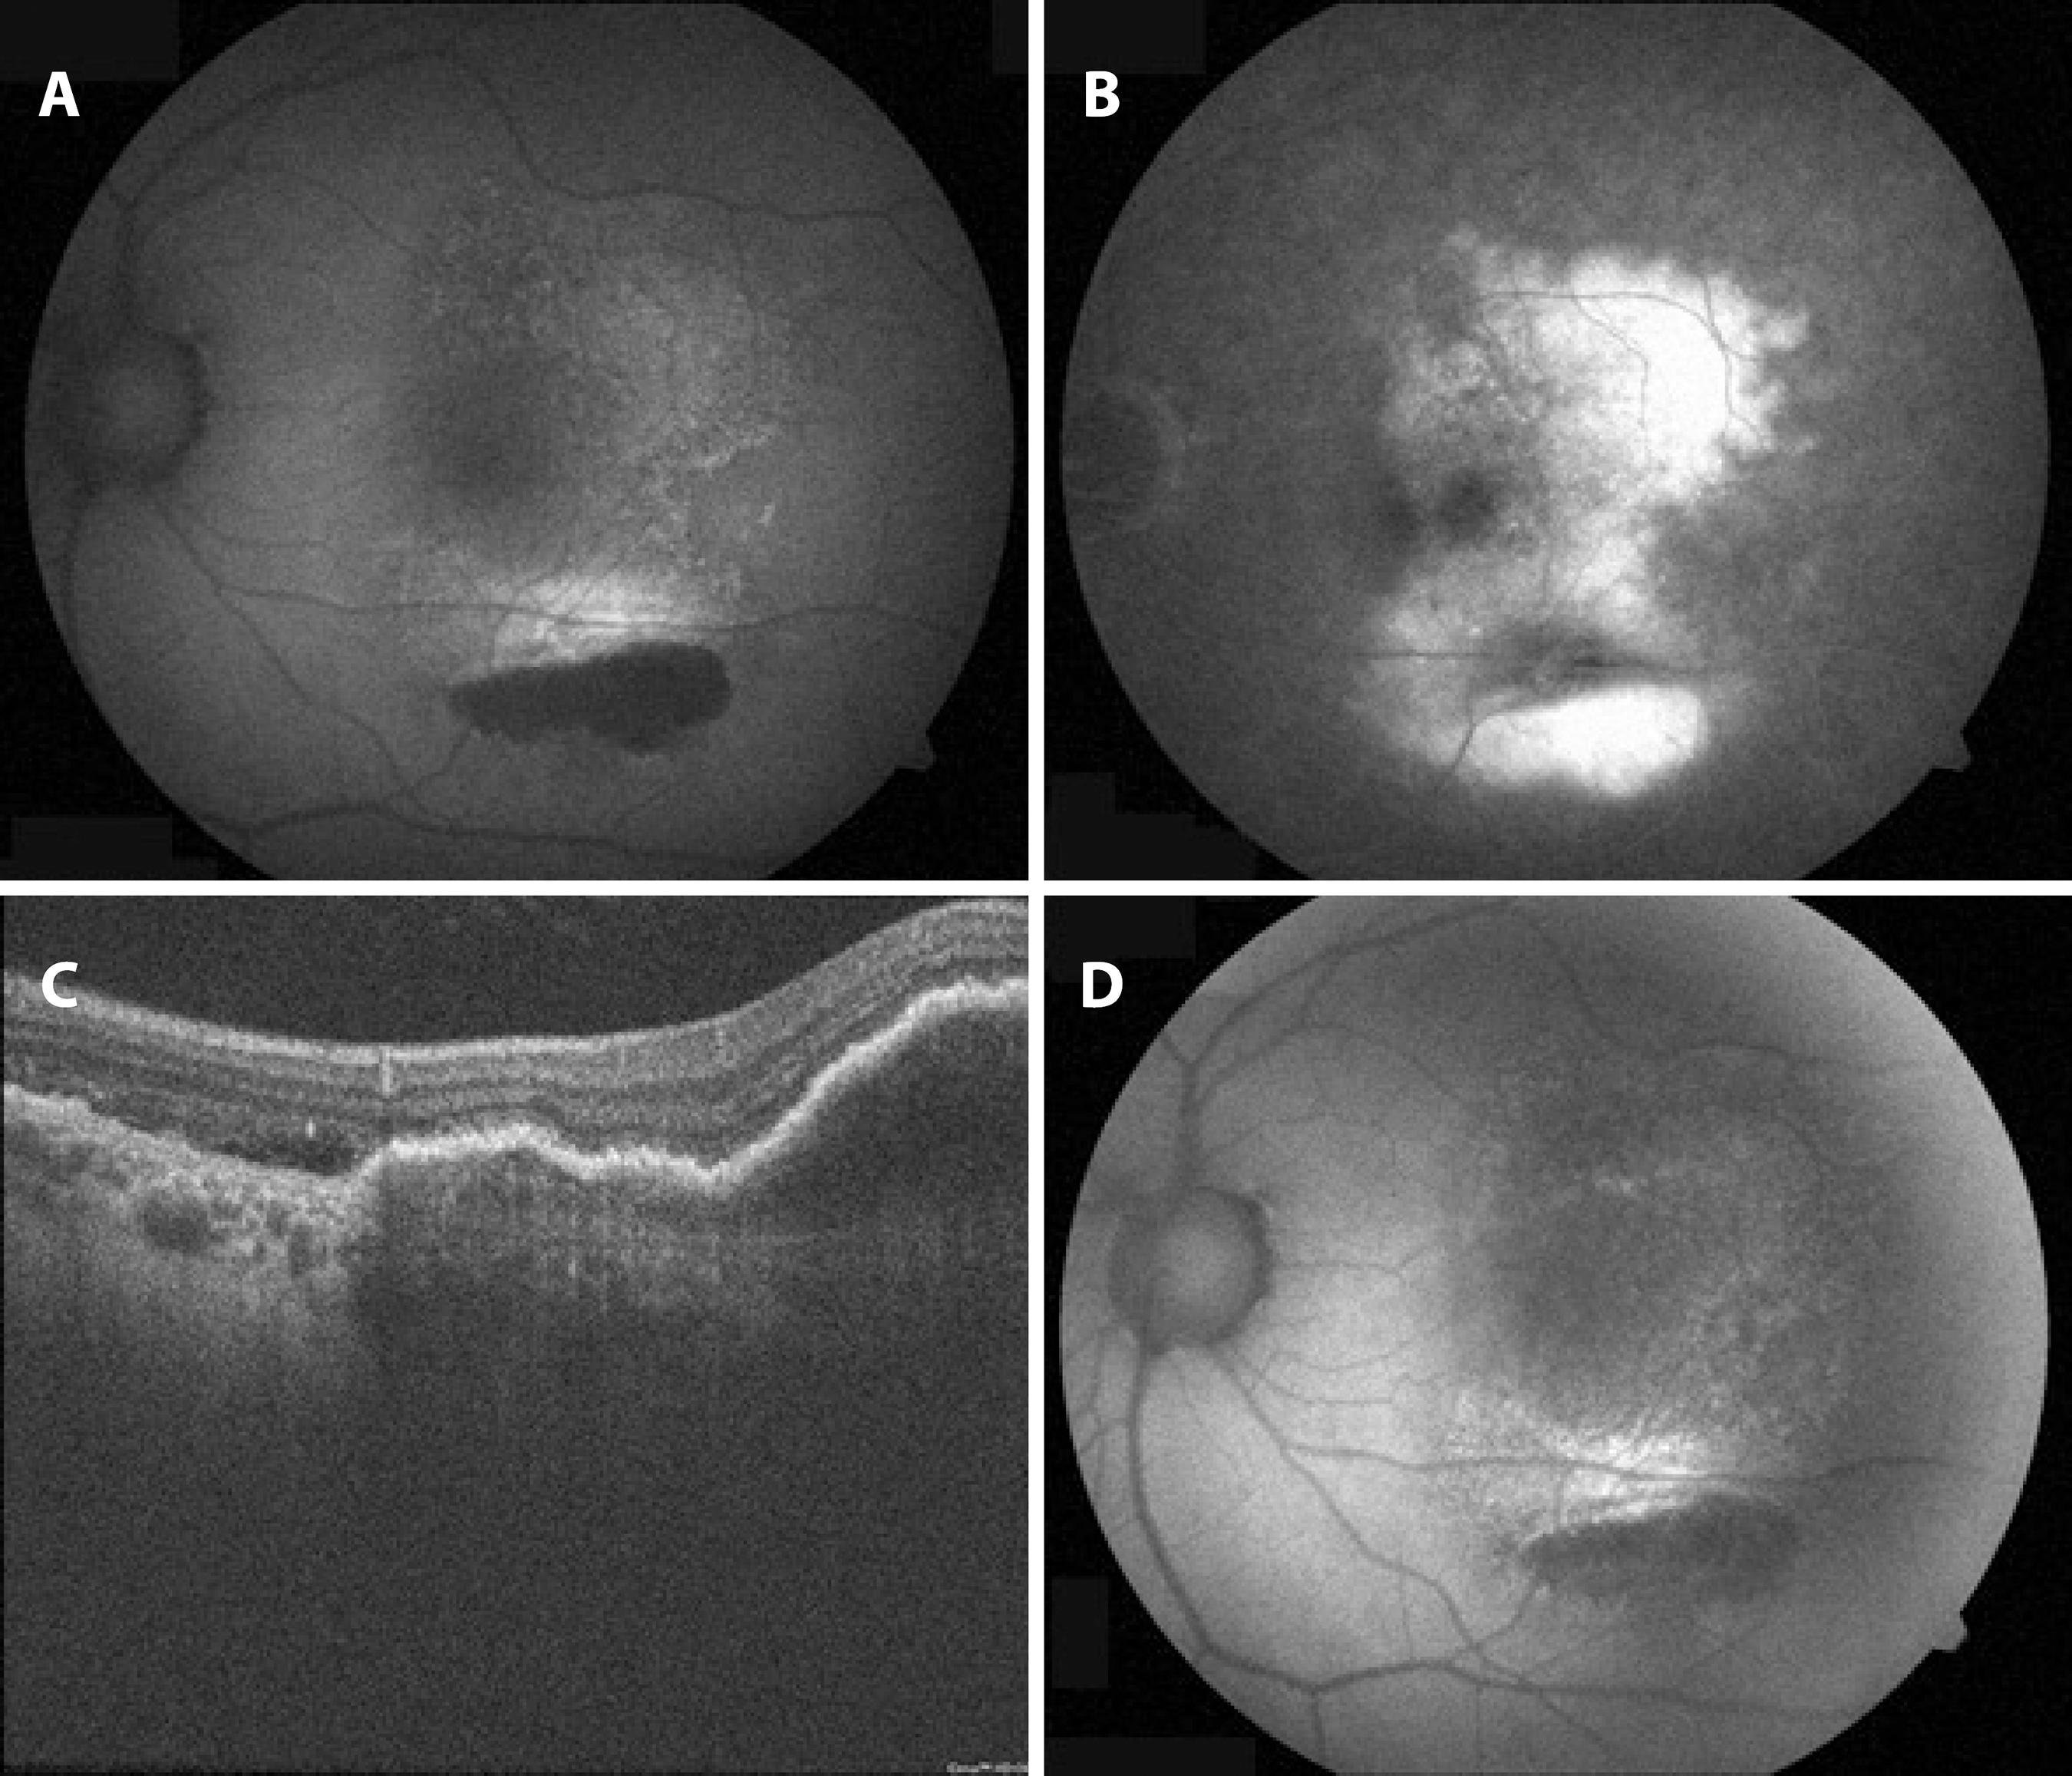

Case 3: A 57-year-old man was admitted to our clinic with vision loss in the left eye. The BCVA in the left eye was 1.0 logMAR. On the basis of the OCT and fundus fluorescein angiography findings, he was diagnosed with AMD, and an intravitreal ranibizumab treatment protocol was started. When his BCVA improved to 0.3 logMAR after the second dose, a Grade 2 RPE tear was observed in the inferior macula. Two doses of ranibizumab were administered after tear formation. Six months later, his BCVA improved to 0.1 logMAR. In fundus autoflorescence imaging, there was hyperautofluorescent spotting in the denuded RPE area, and subretinal and intraretinal hyper-reflective spots were seen in the OCT (Figure 1).

Figure 1 A) Fundus autofluorescent imaging of the left eye in case 3. The retinal pigment epithelium (RPE) tear in the inferior macula is hypoautofluorescent, and the denuded RPE area shows spotted hyperautofluorescence. B) In fluorescein angiography, the RPE tear in the inferior macula is hyperfluorescent, and the denuded RPE area is hypofluorescent. C) The spectral domain optical coherence tomography (SD-OCT) section passes through the RPE tear and pigment epithelial detachment (PED). D) Fundus autoflorescence imaging 3 months after the RPE tear formation.